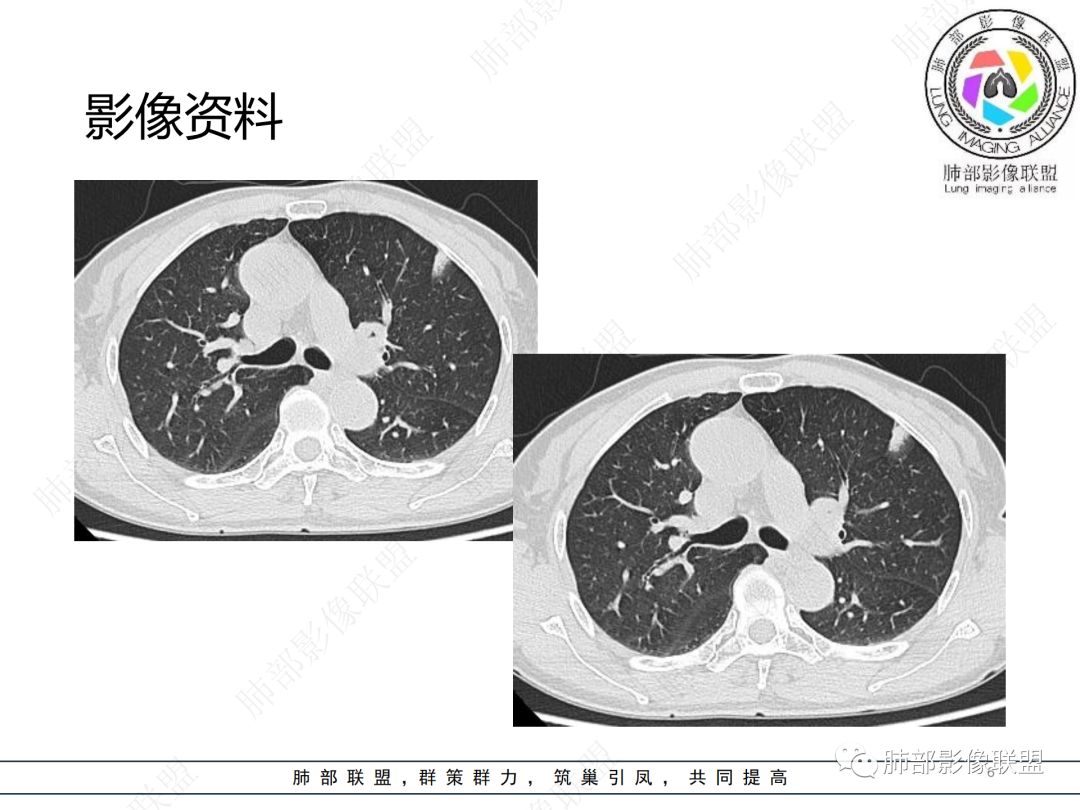

中年女性,咳嗽,胸部CT左肺上叶长条状实变影,周围磨玻璃影,边界清楚,病灶近端似乎有点状高密度影,首先考虑炎性肉芽肿,其次腺癌待排

晨读病例,中年女性,咳嗽一年,左肺上叶胸膜下三角形阴影,局部收缩,周围边缘清晰的磨玻璃影,考虑炎性病变,OP。鉴别腺癌。

左肺上叶胸膜下混合磨玻璃结节,边界似清非清,其内可见增粗血管,抗炎效果差,1年复查增大,考虑粘液腺癌,鉴别慢性炎症

左肺上叶实变影伴磨玻璃影,边界清楚,考虑腺癌,

晨读:慢性病程,胸膜下,边界似清不清,粘液腺癌。

左肺上叶磨玻璃密度,血管增粗,边界清,考虑腺,鉴别炎性

晨读,左肺上叶胸膜下混合磨玻璃密度影,内部可见血管增粗,抗炎治疗效果不佳,一年复查增大,考虑腺癌可能

晨读 左肺上叶胸膜下条片状混杂密度影,膨胀及收缩不明显,周围磨玻璃影边缘似清非清。胸膜糊墙,复查较一年前病灶增大,首先考虑粘液腺癌。

左肺上叶混合磨玻璃病灶,磨玻璃边界似清非清,病灶可见增粗血管,边缘似有月牙征,关键病史与2021年比较有增大,考虑恶性可能大,粘液腺癌、腺癌可能。鉴别慢性炎症。

老年女性,慢性咳嗽,治疗复查无效,咳少量白色粘痰,左肺上叶前段胸膜下亚实性结节,形态呈树上“蘑菇”征,并见“小圆圈”影,周边模糊的磨砂玻璃影,首选粘液腺癌,病灶定位下经皮肺穿刺活检!

晨读:患者,女,65,咳嗽1年,加重1月。胸部CT:左肺上叶胸膜下不规则mGGN,实性灶有膨隆,收缩不明显,周围磨玻璃影似清非清,内可见空泡/细支气管断面?胸膜糊墙。复查较一年前病灶增大。考虑粘液腺癌?鉴别TB、NTM。

晨读左肺上叶胸膜下结节,混合密度磨玻璃,边界似清非清,支气管腔内粘液,警惕粘液腺癌

左肺病灶,周围似清非清,考虑腺癌可能性大,鉴别炎性肉芽肿

左肺上叶混合磨玻璃结节影,部分边缘小叶间隔阻挡,周围磨玻璃影似清非清,内可见空泡,复查较一年前病灶增大。考虑粘液腺癌?鉴别炎性肉芽肿

左肺上叶前段混合磨玻璃结节,实性部分局限性凹陷,磨玻璃影边缘似清非清,老年女性,1年多胸痛病史,考虑腺癌,粘液性腺癌

肺部联盟晨读:老年女性,病程1年,混合磨玻璃密度,周围边缘较清楚,腺癌>炎症

晨读老年女性,左肺上叶胸膜下条状实变影,周围可见絮状磨玻璃影,边界较清,可见小叶间隔阻挡月牙征,抗炎无效,复查增大,考虑腺癌。

左肺上叶结节影,周围边界清楚磨玻璃影,考虑粘液腺癌

左肺上叶胸膜下混合磨玻璃结节,边界不甚清楚,抗炎无效,目前增大,考虑粘液腺癌

左肺上叶混合密度的结节,部分磨玻璃边界偏清晰,内部血管似有增粗,病灶较一年前增大,肿瘤要警惕。

左上叶混杂密度结节,边界似清非清,其内血管影增粗扭曲,年度复查增大,白色粘液痰,有树上蘑菇征?综合分析考虑结节型粘液腺癌

混合磨玻璃结节,密度不均,短毛刺,周围磨玻璃边界较清,复查病灶增大,考虑腺癌,鉴别炎性肉芽肿。

左肺上叶混合结节伴磨玻璃影,边界清楚,考虑腺癌

这个要做个重建就好了  可以整体观察这个病灶 1.边界清  2复查有增大,考虑恶性是有可能的

晨读,混合磨玻璃结节,内见增粗血管影,病史长,结节型粘液腺癌,抗炎后短期复查。